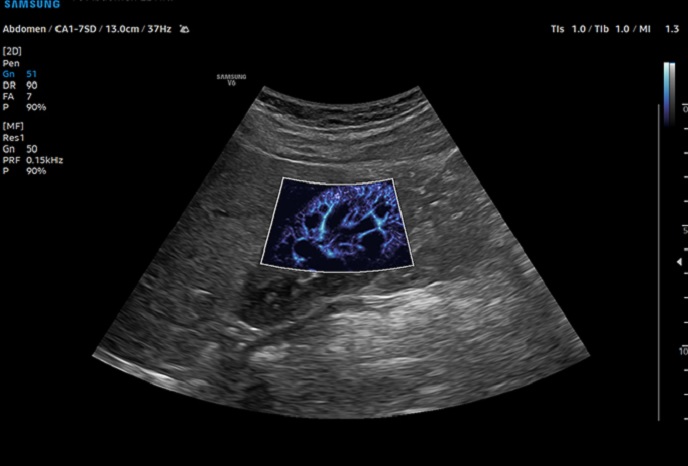

고급 도플러 기능으로 심혈관 평가 및 이상 감지

미세혈류 플로우

루미플로우

S-플로우

심장심장의 해부학 구조 및 혈류역학적 평가, 순환기계 장애, 심장 수축·이완